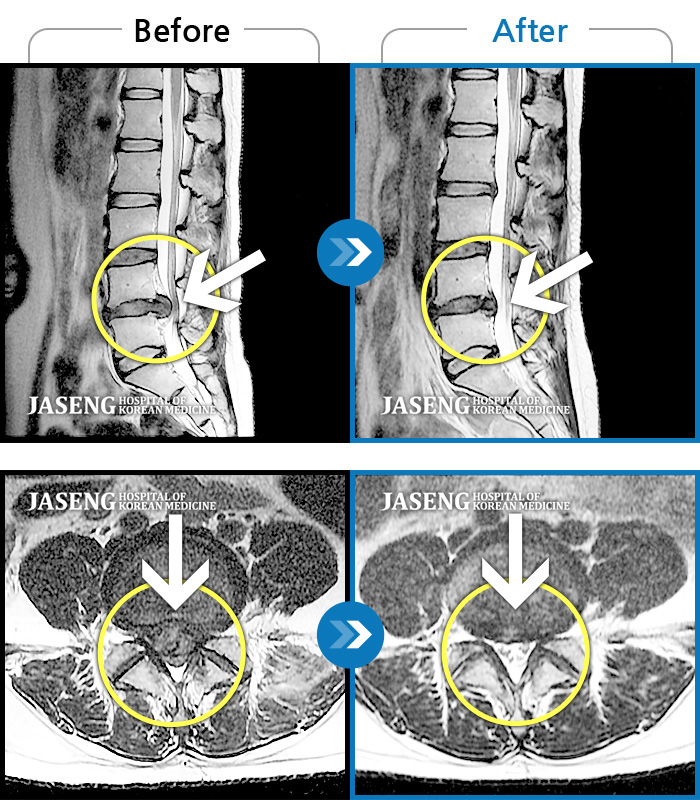

MRI 치료사례

일상생활 불가능한 통증으로 본원에 입원 위해 내원